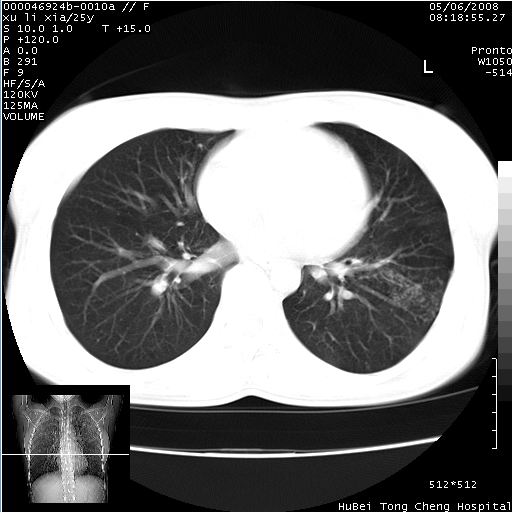

患者 女,25岁。因“左侧卵巢肿瘤”术前胸片偶然发现两肺病变。平素无明显不适,无呼吸系统症状及体征,无传染病史。

cr x线胸片提示:两肺感染性病变(结核可能性大)。

胸部ct轴位平扫(层厚10mm,螺距1.5,重建间隔10mm),图像如下:

(注:上级医院会诊胸部ct片——考虑为肺部真菌感染。)

病灶呈地图样分布于肺外围,与正常组织分界清晰+弥漫性磨玻璃影中见小叶间隔增厚呈碎石路样表现+年轻女性,无明显临床症状=肺泡蛋白沉积症?

双肺上叶可见节段性渗出性病变,可见树芽征像,左肺下叶背段可见结节影。

病灶呈离心性分布,以两上肺多见,远离肺血管纹理,有部分肺间质条索影,病人症状轻微,考虑结节病。